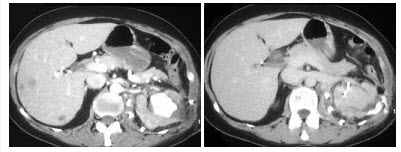

11、单项选择题

男,59岁,右侧髋骶部持续性疼痛,夜间加重,2月前被确诊为肾细胞癌,结合图像,最可能的诊断是()

A.骨肉瘤

B.骨巨细胞瘤

C.骨囊肿

D.骨转移瘤

E.骨瘤

点击查看答案

本题答案:微信扫下方二维码即可打包下载完整带答案解析版《★放射医学(医学高级)》或《放射医学(医学高级):CT》题库